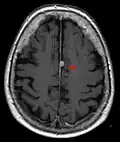

T1 (note CSF is dark) with contrast (arrow pointing to meningioma of the falx) -

- T1-weighted (T1W) images: Cerebrospinal fluid is dark. T1-weighted images are useful for visualizing normal anatomy.